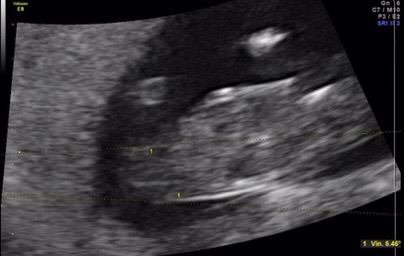

I know it's really too early. But I also know there are great gender guessers out there.

Sonographer examined for an hour in total, and was "leaning" girl.

He confirmed gender in My last pregnancy at 11 weeks 5 days